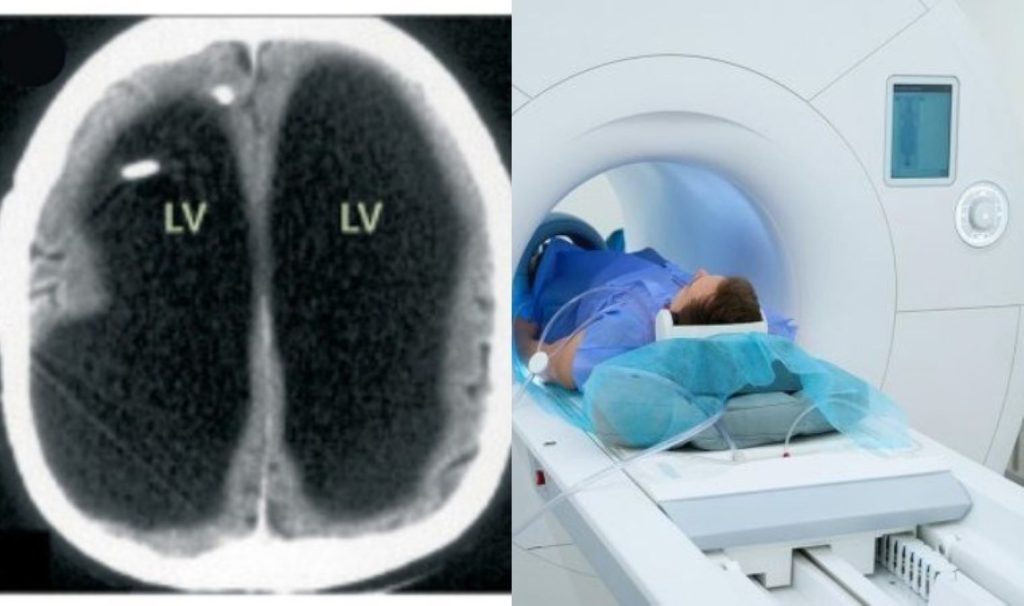

Hastaya yapilan ct ve mRI taramalarda hekimler inanilmaz bir otörmle karşilaşti: beyninürünk bir kserin yerinde yoktu, bunun yerine devasa bir bir sı sı cebi bulunUyu. İpucu Dunyasinda Hayli Ender Ender Ender Gör bir bir Durum Olan Önemli Hidrosefali Taşhisi Konuldu.

İpucu Derdi Lancet’de Paylaşilan Beyin Taramalarda, Beynin Ana Börgesinin Buyuk Ölçüde Siyah Görütkaoğü, Bunun da Sizi Birikimine Işaret Etti. BU DURUM, BEnINININ SIŞAKAK INCE Bir Katman Halinde Kafatasinin Kenaria Itilmesine Neden Olmiştu.